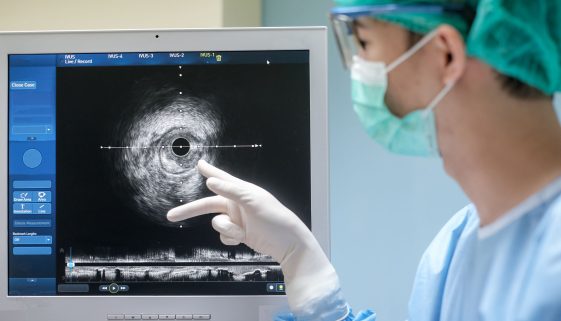

التقرحات والأورام الهضمية تمثل تحديات صحية يمكن أن تؤثر بشكل كبير على جودة حياة الأفراد. يعتمد الشفاء الناجح ونتائج العلاج بشكل كبير على الاكتشاف المبكر لهذه الحالات. في هذا المقال، سنستعرض أهمية الاكتشاف المبكر، ونقدم نصائح وتعليمات تثقيفية تساعد الأفراد في معرفتها وإدارتها بفعالية. ما هي التقرحات والأورام الهضمية؟ التقرحات […]